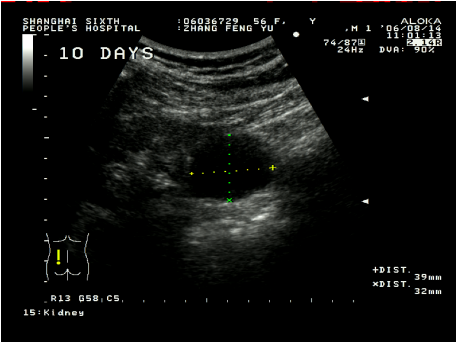

超聲引導下腎囊腫穿刺硬化治療具有簡單易行,患者少痛苦,復發率低,費用低等優點。這種方法是用超聲診斷儀事先選定穿刺點,設計好進針角度和進針深度,在局部麻醉下,用專用的穿刺探頭,根據已設定的角度和深度把直徑0.8毫米或1.2毫米的針插入囊腫,因為囊腫、針道和周圍臟器全部在超聲屏幕上看到,所以不會損傷周圍臟器,待抽凈囊液后,注入硬化劑,使硬化劑與囊腫內壁上皮接觸,達到硬化效果,數分鐘后把硬化劑抽出,拔出穿刺針,整個治療過程安全。在硬化治療后的早期(一個月內),一般說,囊腫上皮因硬化劑燒灼作用,會有滲出,一個月后開始漸漸吸收,三個月后明顯縮小,直至囊腫完全消失。

術后10天囊腫已縮小到30mm左右